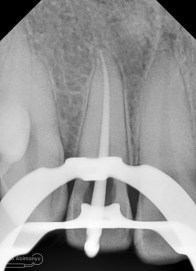

Irigasi menggunakan larutan NaOCl 5,25% dan diaktivasi menggunakan ultrasonic dengan tip Irrisafe, setelah beberapa sequence selama hampir 40 menit kemudian dilakukan pengepasan guttap utama dan dironsen.

Dari ronsen semuanya terlihat sudah oke… dan siap dilakukan pengisian…

Tehnik pengisian saluran akar yang digunakan adalah Continuous Wave Condensation dengan alat Element Obturation Unit (SybronEndo)